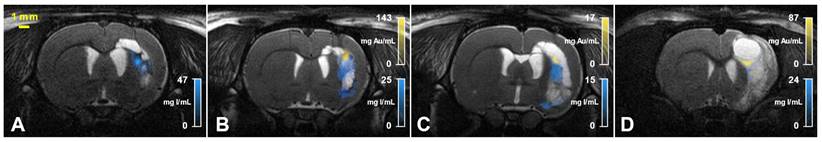

Figure 4

SKES-CT allows specific imaging of gold, iodine and their mixtures in vivo and may serve as a method of reference for SPCCT: back-to-back imaging of rat brain with a focal cerebral injury post-transplantation of AuNP-labelled macrophages embedded in INP-labelled scaffold using SKES-CT (A-D) and SPCCT (E-H). A: Synchrotron conventional images acquired at 4 different energies, above and below gold and iodine K-edges (top-left: 32.9 keV, top-right: 33.9 keV, bottom-left: 80.2 keV, bottom-right: 81.2 keV). B: SKES-CT iodine concentration map. C: SKES-CT gold concentration map. D: Synchrotron SKES-CT 3D view of segmented bone (white), iodine (blue) and gold (yellow). E: SPCCT conventional image. F: SPCCT iodine concentration map. G: SPCCT gold concentration map. H: SPCCT 3D view of segmented bone (white), iodine (blue) and gold (yellow). White arrow on D shows iodine detected by SKES-CT and not by SPCCT.

Nanotheranostics Image

Figure 4E shows conventional SPCCT images obtained in rat shown in Figure 4A-D. Figure 4F-G shows element-specific maps (iodine and gold) and Figure 4H shows the segmentation of iodine and gold signals in 3D. As for SKES-CT, gold can be distinguished from iodine, in the iodine and gold concentration maps only. SPCCT concentration maps were noisier than those obtained with SKES-CT (for instance, sigma in brain parenchyma = 2.81 mg/mL for SPCCT and 0.39 mg/mL for SKES-CT in gold concentration images, respectively, Figure 4C and 4G). On visual assessment, SPCCT properly localized gold (Figure 4G vs Figure 4C), while it missed part of iodine compared to SKES-CT (Figure 4F vs Figure 4B and Figure 4H vs Figure 4D arrow).

SPCCT quantification of gold mass was in good agreement compared to SKES-CT (R² = 0.94, slope of 0.95 and bias of 3 µg with limits of agreement [-12; +15] µg, Figure 6A-B), over the range studied (0-140 µg). Furthermore, the presence of iodine in a voxel containing gold did not impact SPCCT gold quantification: belonging to the bicolor or monocolor groups had no effect on performances, as seen in Figure 6A-B. For iodine mass measurement, SPCCT measurements were more dispersed than gold data compared to SKES-CT (R² = 0.59, slope of 1.08 and bias of -9 µg with limits of agreement [-40; +26] µg) (Figure 6C-D).